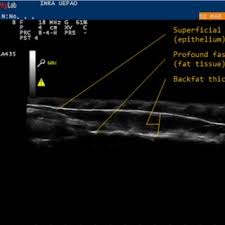

경동맥 초음파 검사는 고주파 초음파를 사용하여 목의 경동맥 혈관을 영상으로 확인하는 검사입니다. 혈관 내벽 두께, 혈류 흐름, 좁아진 정도 등을 실시간으로 볼 수 있으며, 조영제나 방사선 노출이 없어 안전합니다. 검사 시간은 약 20~30분 정도 소요됩니다.

혈관 내막 두께, 협착 정도, 혈류 속도 등을 확인할 수 있으며, 결과에 따라 추가 정밀검사가 필요할 수 있습니다.